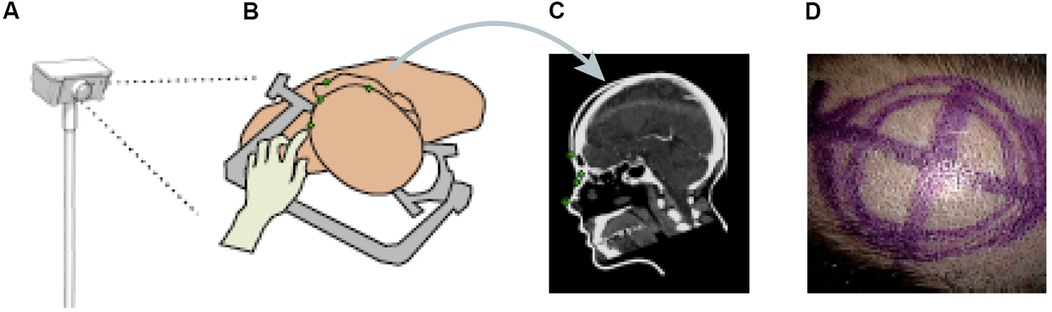

Other papers have also proposed ML methods to track objects or hands' movements in surgery. Kögl et al. published a study in 2022 describing the use of ML to track the movements of hands via hand topology (8). This tool-free neuronavigational method focused on 21 landmarks assigned to a hand and used real and synthetic images to train 2 deep learning networks to estimate hand pose. Real images were used to understand the 2-dimensional coordinates of the hand, whereas synthetic images were used to train the model on relative depth. The Google MediaPipe ML framework was implemented to determine the 2.5-dimensional hand pose. However, the aim was to estimate the 3D pose. Therefore, once these images had been used to train the neural networks, solving the Perspective-n-Point problem was then necessary. This was done by determining where the hand was in space relative to the frame, allowing the determination of the 3D hand pose. Once the 3D hand pose had been estimated, these coordinates were inputted into the 3D Slicer using the OpenIGTLink. The overall aim was to have tool-free neuronavigation that would allow the estimation of hand pose to allow neurosurgeons to use their fingertips to plan craniotomies instead of conventional pointers (Figure 12) (8).

Figure 12. Machine learning (ML) application in neurosurgery tool-free methods. In an ML-based hand pose estimation study, Kögl et al. (8) presented a new tool-free neuronavigation method using an RGB camera during burr hole placement. This figure shows the stepwise process used to track hand motion for landmark selection. (A) Illustration of the monocular RGB camera used for this experiment to capture the motion of the hand. (B) Illustration of the hand being used to select landmarks for burr hole placement. (C) Computed tomography showing predefined anatomical landmarks. (D) Photograph showing the final position of the burr hole placement for a craniotomy using this system. Used with permission from Kögl FV, Léger É, Haouchine N, et al. A Tool-free Neuronavigation Method based on Single-view Hand Tracking. Comput Methods Biomech Biomed Eng Imaging Vis. 2023;11(4):1307–1315. doi:10.1080/21681163.2022.2163428.